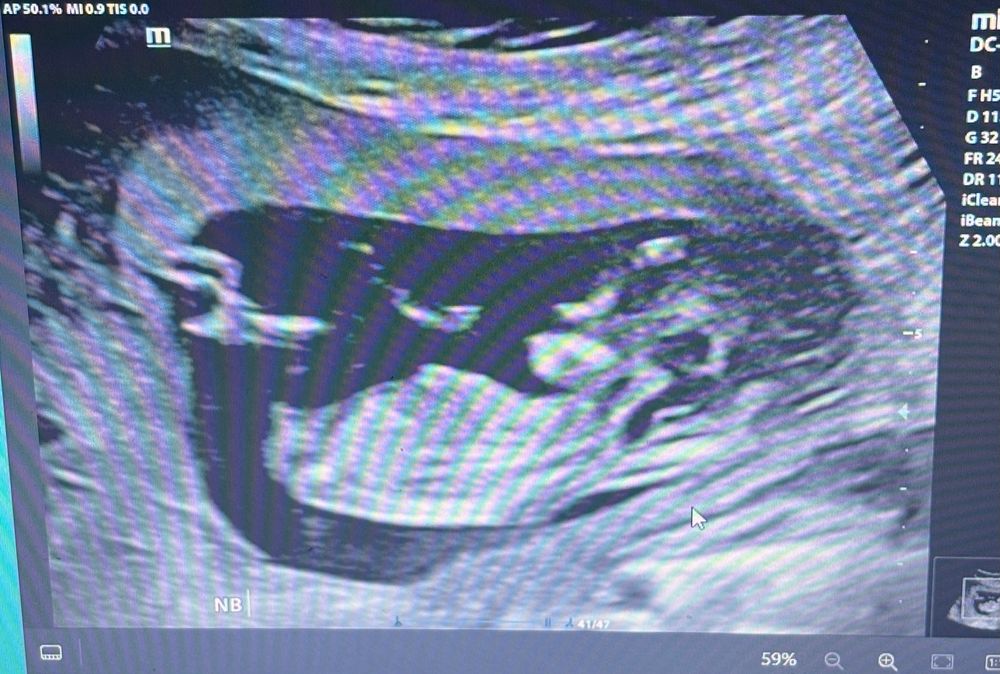

Вторая беременность, очень интересно хоть предположить, кто же будет) может, кто-то понимает по узи на 12 неделе, как думаете, кто на фото? Заранее спасибо!

Это мальчик. У девочек половой бугорок идет параллельно спинке, а здесь конкретный торчун)